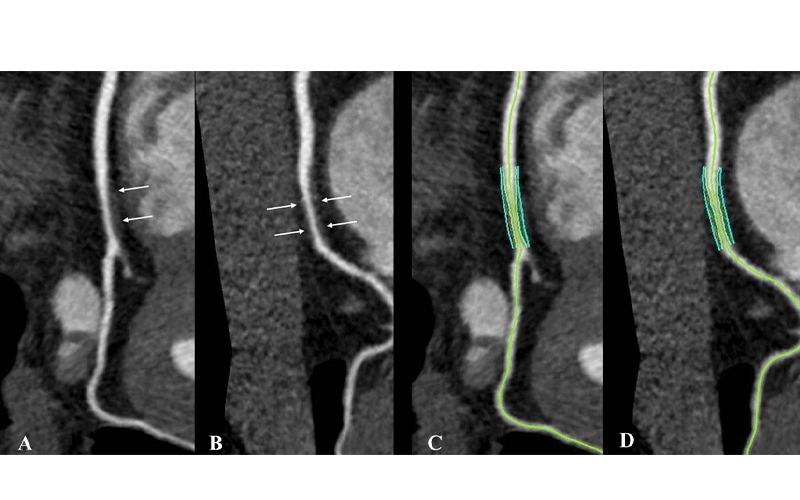

All 265 participants underwent coronary artery calcium scoring. Most of the participants also had coronary CT angiography. Image assessors who had been blinded to the clinical characteristics of the participants and their HIV status used the CT angiography results to categorize the coronary plaques as calcified, noncalcified or mixed.

However, noncalcified plaque prevalence and volume were two to three times higher at coronary CT angiography in people living with HIV compared with non-HIV healthy volunteers after adjustment for cardiovascular risk factors. Noncalcified plaque may be more prone to rupture than calcified plaque.

Calcified plaque frequency was reduced in people living with HIV. Treatment with protease inhibitors was associated with higher volume of overall and mixed plaque.

“For radiologists, these results suggest that coronary CT angiography interpretation in people living with HIV should probably include quantification of coronary plaque by subtypes to allow better cardiovascular risk stratification,” Dr. Chartrand-Lefebvre said.